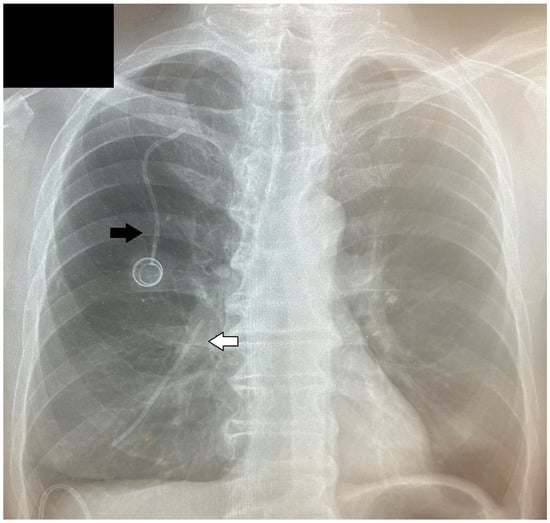

| Presented case | M | 67 | Gastric cancer | Cough, weakness, nausea, and heartburn | Right pulmonary artery | 8 | Thoracotomy |